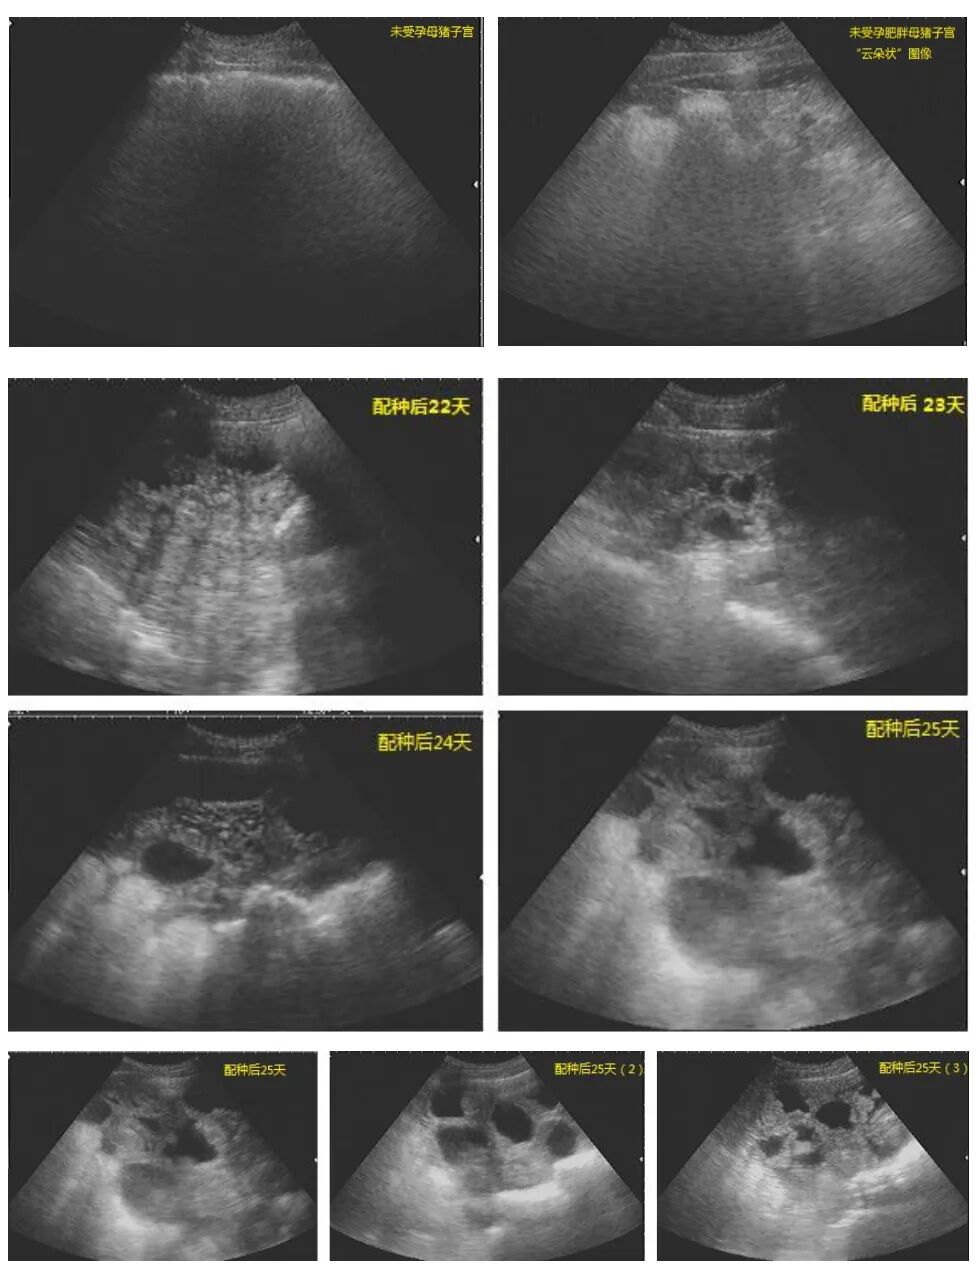

(1)查返情:配种后第18-24天,细致观察母猪行为、外阴变化,判断是否返情,及时淘汰未孕母猪,缩短非生产天数。

(2)妊娠确认(可选但推荐):配种后第25-30天,用B超复查妊娠,对未孕母猪及时处理,减少饲料浪费。